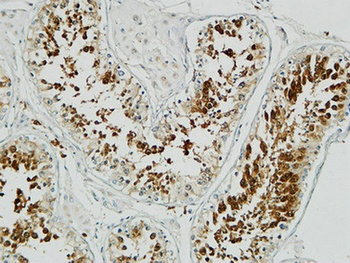

Immunohistochemistry analysis of paraffin-embedded human breast carcinoma tissue, using p18 INK Antibody. The picture on the right is blocked with the synthesized peptide.